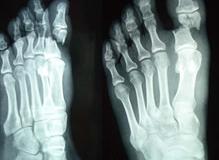

骨折顾名思义就是指骨头或骨头的结构完全或部分断裂。多见于儿童及老年人,中青年也时有发生。病人常为—个部位骨折,少数为多发性骨折,经及时恰当处理,多数病人能恢复原来的功能,少数病人可留有不同程度的后遗症,骨折发生后,离医院较近者,可直接送医院或叫救护车,离医院比较远的病人,必须进行简单的处理,以防在送医院途中加重病情,甚至造成不可逆的后果。